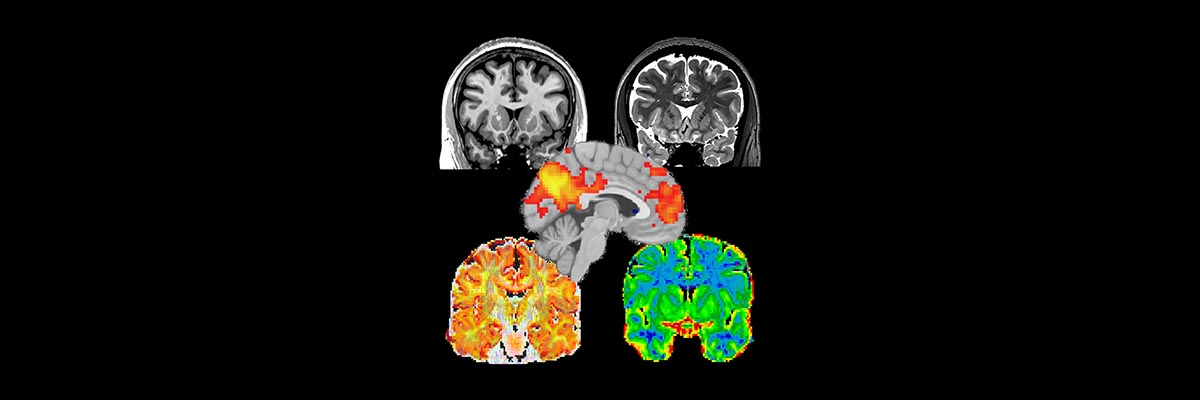

The protocol generates T1-weighted data; T2-weighted data; diffusion data suitable for both DTI and NODDI analyses, as well as for probabilistic tractography, and the corresponding distortion correction data; MT-sat data and a B1-map that together with the NODDI data can be used to produce a g-ratio map; and resting state fMRI data. A description of the sequences that produce each sort of data, with notes for the MR technicians, can be found here.